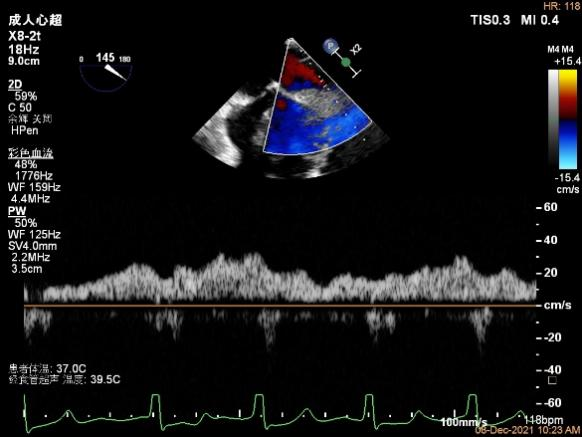

X-plane:下夹子尝试先捕获2区瓣叶

夹子关闭过程中,Color提示2区反流逐渐减少,残余反流位于夹子外侧

第一个夹子放置侯二尖瓣口平均跨瓣压差:4mmHg

肺静脉血流频谱恢复正向

x-plane验证前后叶抓捕后bond明显